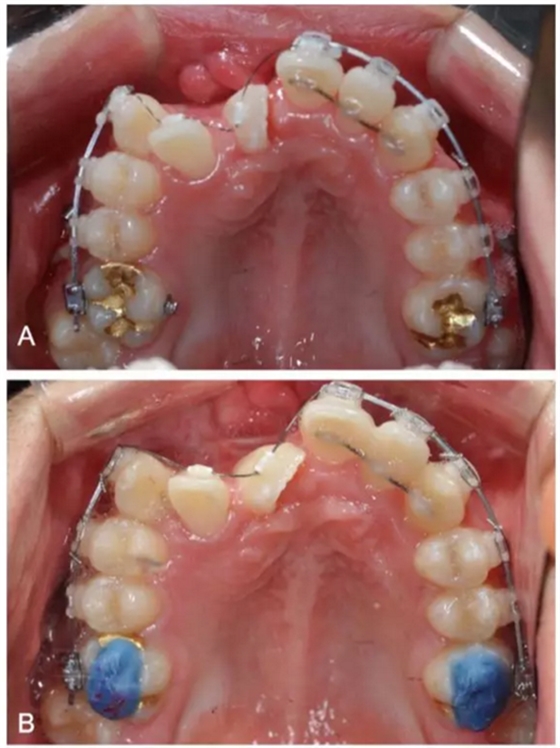

一期手術(shù)主要是牽引側(cè)切牙和尖牙:于上頜前牙區(qū)唇側(cè)作切口,翻全厚瓣;腭側(cè)面較小;在尖牙唇側(cè)、側(cè)切牙腭側(cè)粘扣掛結(jié)扎絲牽引,通過一輔助鈦板及樹脂等連接至弓絲上;采用閉合式導(dǎo)萌技術(shù),將皮瓣復(fù)位縫合,僅結(jié)扎絲穿過粘膜;2周內(nèi)軟組織得以愈合,牽引開始。先通過正畸力,近中移動(dòng)側(cè)切牙,遠(yuǎn)中移動(dòng)尖牙。10個(gè)月后,阻生牙牙冠萌出,側(cè)切牙、尖牙的易位得以矯正。

二期手術(shù)主要是牽引中切牙:于上頜前牙區(qū)腭側(cè)作切口,翻全厚瓣,在切牙唇側(cè)粘扣掛結(jié)扎絲牽引;軟組織愈合后,牽引開始。為施加合適的垂直向力,在下頜前牙區(qū)放置C型管,掛橡皮筋牽引。14個(gè)月后,切牙牙冠萌出。使用mini管代替托槽,對切牙、尖牙進(jìn)行矯治;矯治過程采用輕力,0.014-in鎳鈦絲。